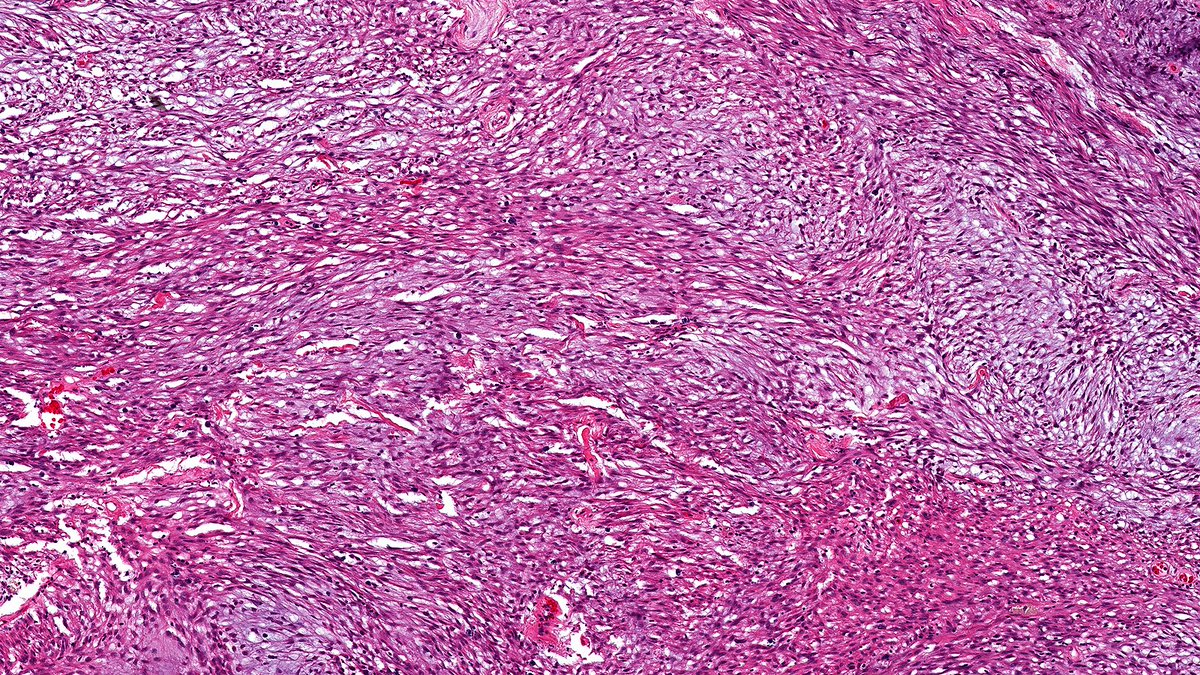

🫘Severe hypertension, Kidney: ⭐️Myxoid intimal hyperplasia of arteries (left, H&E), the lumens are reduced to pinpoint slits 💡Onion skin thickening of the arteriolar wall (right, PAS) 🔬Both images contain a sclerotic glomerulus – the end-effect of chronic ischemia #PathTwitter